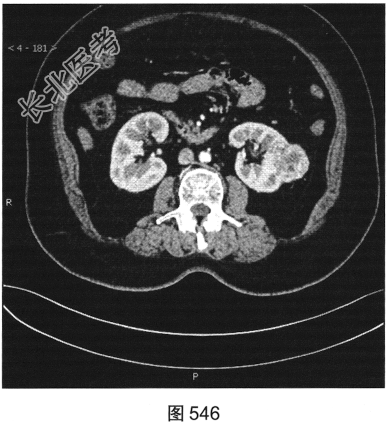

- 多项选择题3.[提示]CT平扫+增强(图545~图549):左肾下极背外侧软组织密度灶, 部分突出于肾实质外,其内可见低密度坏死灶, 增强扫描强化不均匀,平扫、皮质、实质、排泌CT值36HU、92HU、73HU、53HU。可考虑的鉴别诊断为( )